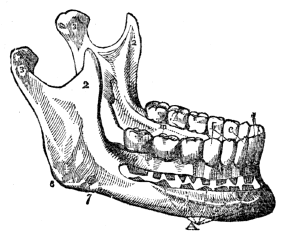

| 12. | Anatomy of the Teeth, | 105 |

| 12. | Physiology of the Teeth, | 109 |

| 12. | Hygiene of the Teeth, | 110 |